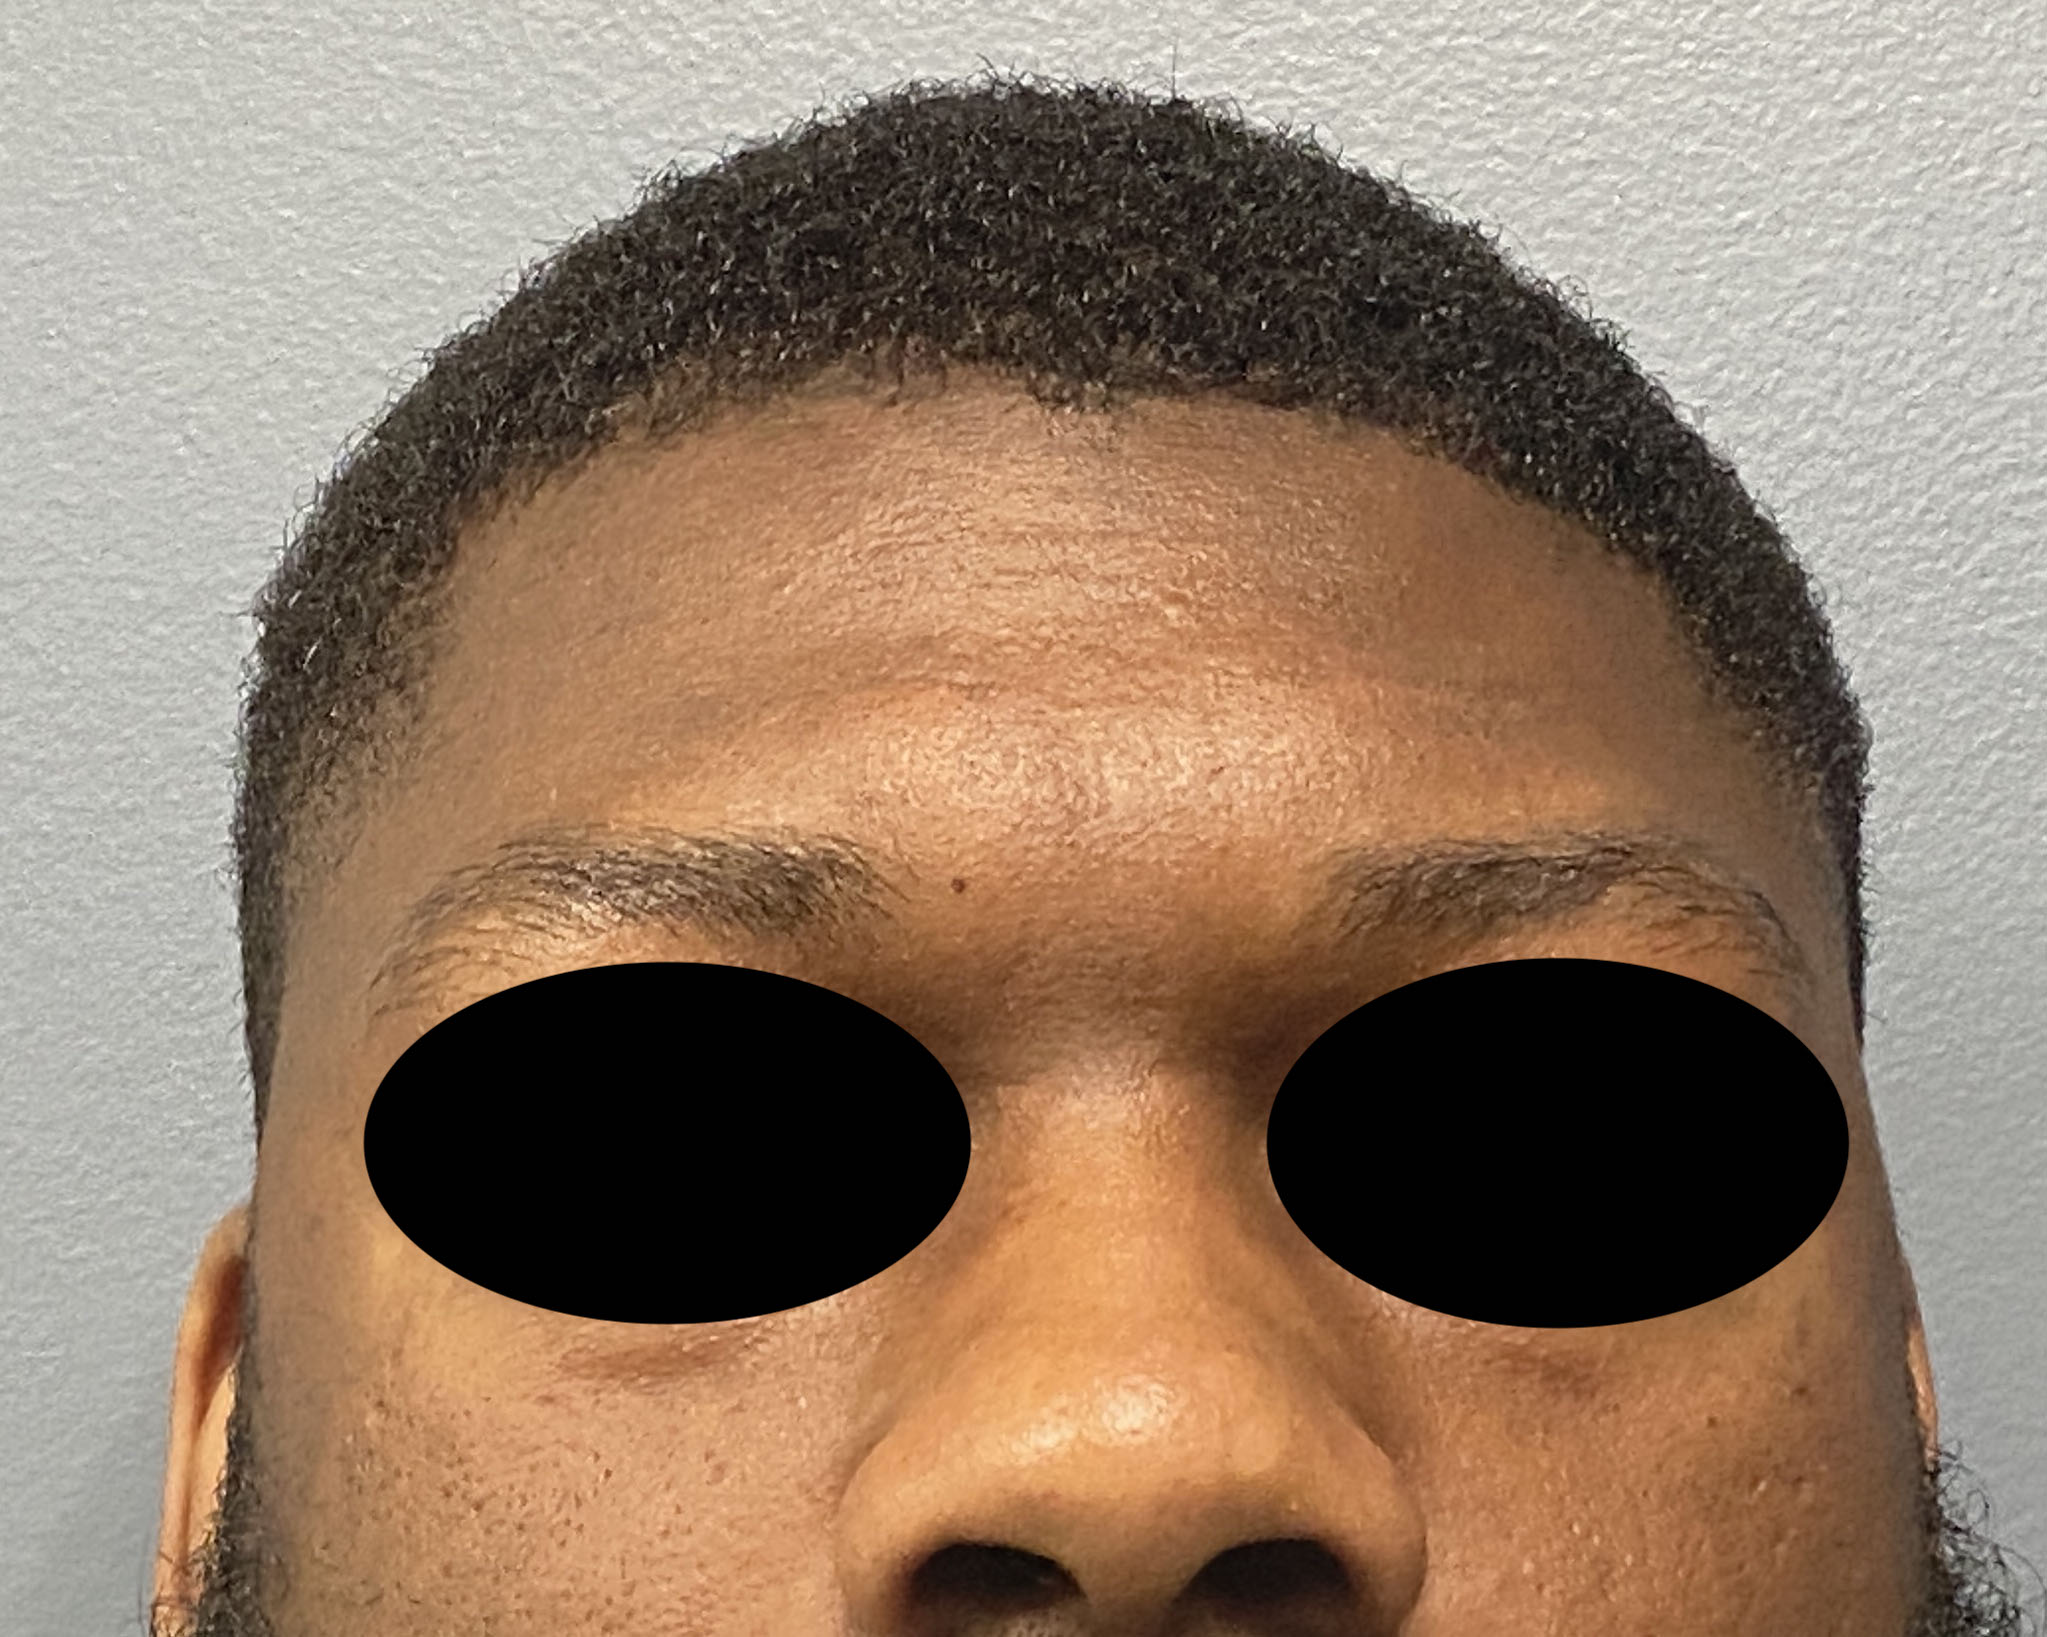

Desire to build up the flatter upper part of the back of his head.

Upper occipital skull augmentation using a custom skull implant.

Desire to build up the flatter upper part of the back of his head.

Upper occipital skull augmentation using a custom skull implant.